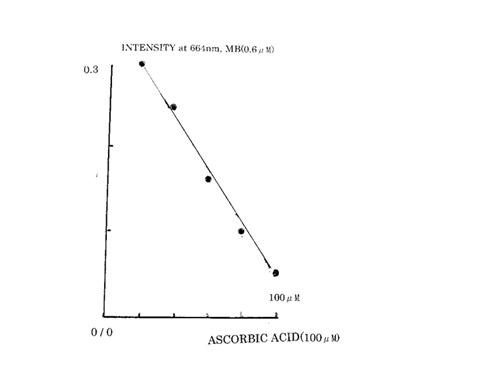

The absorbance of oxidized MB was measured at 664nm.

Oxidized MB was reduced gradually to leuco-MB after adding L-ascorbic acid ( Fig.2 ).

( Fig.2 )